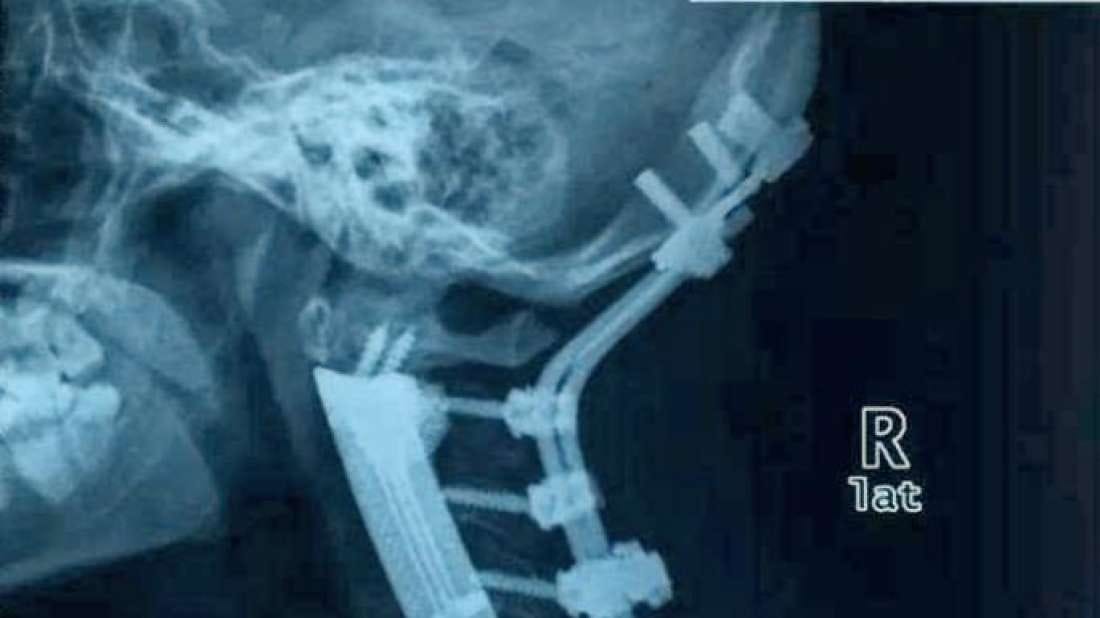

Il cancro canino può essere il peggior incubo dei proprietari di cani e pochi altri tumori sono terrificanti quanto il cancro alle ossa L'osteosarcoma è la forma più comune di tumore osseo nei cani, che rappresenta circa l'85% dei tumori ossei totali È aggressivo, veloce da diffondere o metastatizzare e difficile da trattare. Tumore ai polmoni sopravvivenza Il tumore al polmone ha vari stadi, in base ai quali si decide la terapia adeguata Quando ci si trova davanti al primo e al secondo stadio, un intervento. Berkeley Electronic Press Selected Works.

Fatti p > cancro alla spina dorsale canina è più frequente tra i cani più di sei anni La maggior parte dei tumori spinali sono in gran parte a causa della maggiore pressione sulla colonna vertebrale a causa di un tumore adiacenti all'interno dell'osso. Come diagnosticarlo Il lipoma alla schiena è un tumore generalmente asintomatico, pertanto per scoprire se si è affetti da questa neoplasia benigna è necessario sottoporsi ad alcune indagini cliniche con l'impiego di strumentazioni Un'ecocardiografia mostra evidenti i contorni del lipoma sul referto compare la massa alla schiena, anche se i contorni non saranno ben nitidi. Considerati da un punto di vista “tecnico”, essi rappresentano il 15% dei tumori del sistema nervoso centrale A seconda dello sviluppo si distinguono in intramidollare (5%) – nel midollo, intradurale extramidollare (fuori dal midollo ma all’interno delle meningi), con possibile estensione extradurale (40%), ed extradurale (55%) (all’ interno del canale vertebrale, ma fuori dal.

Mi e'stato diagnosticato un tumore alla spina dorsale vorrrei sapere se ci sono cure adeguate e quali sono Risposta del 24 ottobre 05 Risposta a cura di Dott MATTEO LIBROIA Sarebbe utile una visita specialistica neurochirugica, anche perchè non è specificato il tipo di neoplasia descritta. Fatti p > cancro alla spina dorsale canina è più frequente tra i cani più di sei anni La maggior parte dei tumori spinali sono in gran parte a causa della maggiore pressione sulla colonna vertebrale a causa di un tumore adiacenti all'interno dell'osso. Il tumore alla spina dorsale comprende un tumore alle ossa Tumori al fegato,polmoni e ossa sono tra i peggiori esistenti in natura Stagli vicino e dagli tanto tanto conforto!!!.